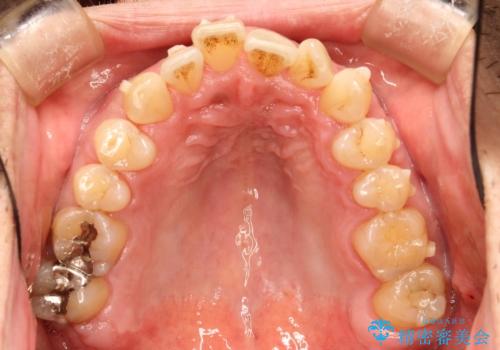

インビザライン invisalign ガタつきを治すマウスピース矯正

- 非抜歯・上顎臼歯遠心移動によるマウスピース矯正を計画した。

ガタつきを取り除くだけであれば非常に簡潔であるマウスピース矯正ですが、奥歯の位置関係の是正や、垂直的な歯の位置のコントロールなどが計画に含まれる場合、治療が難しくなってきます。